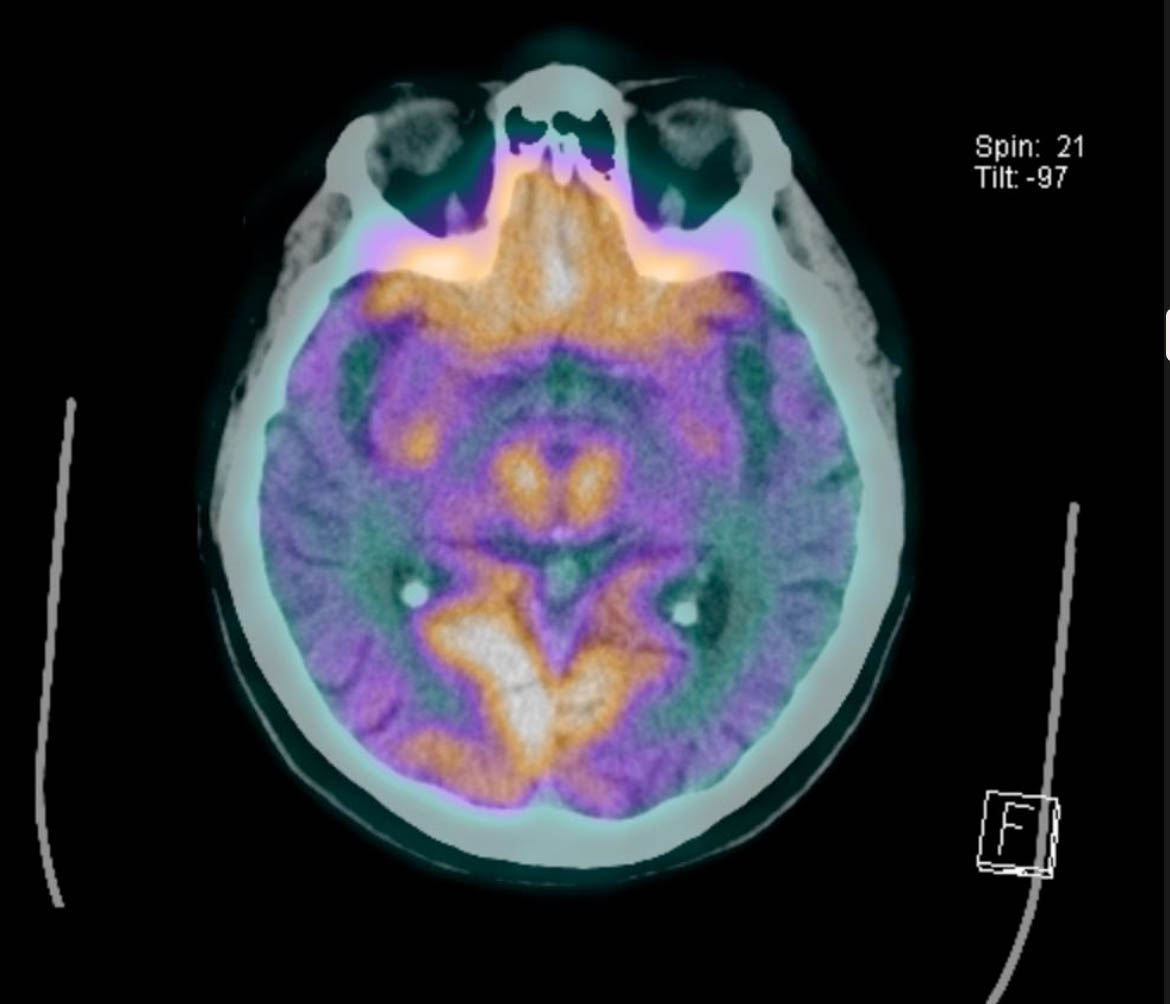

Imagen de PET CT en enfermo con Alzheimer en que las zonas de color naranja son normales, pero extensas zonas de su corteza cerebral no se aprecian del mismo color ( zonas de daño ).

No menos importante, es la incorporación de los estudios PET CT de cerebro( examen que usa la fusión del scanner, con uso de sustancias radiactivas de muy baja dosis), que permiten visualizar áreas del cerebro con menor actividad metabólica lo que indicaría daño de las neuronas y pérdida de éstas. También permiten evaluar resultados de tratamientos al apreciarse zonas cerebrales con mejor actividad metabólica.